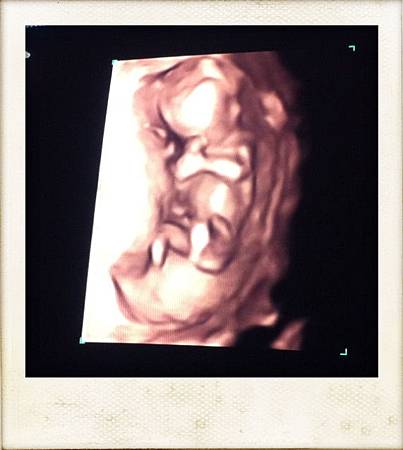

於是就躺在超音波的床上,護士小姐要我把肚子那塊”清空”,她再用一條毛巾包塞在褲緣並蓋上另一條在肚子上(個人覺得這幾個動作滿細心的),躺在那仔細觀察環境四週,天花板上還有類似像星星一點一點的燈,彷彿就是躺在那看星星(真貼心),而除了床旁邊那台的大機器的螢幕外,躺著的正前方也有一台電視螢幕可供媽媽看!!可說是有精心設計又有人情味的實驗室啊!!!過了一會兒我們的超音波師就進來那微暗的房間,一大早嚼著口香糖還頂著有點像貝克漢的頭,很有精神的樣子!!而且發我的中文名字非常正確(加分),把毛巾掀開後就把照超音波的膠擠在我肚皮上,記得以前在台灣作超音波都是冰冰的膠,今天這個還熱熱的耶,難不成他們還加熱?真的有用心!!!!於是邊照就邊跟我們解釋,最主是要測baby頸後透明帶厚度,當然也show給我們看baby的頭,兩隻手臂,兩隻腳,心臟等,由於這是我們第一次照這種大台的儀器,所以很精密,看得超清楚的,而且整個就是”人型”出現啊,好奇妙的感覺啊!!!!!!就是有個長得像人的人住在我肚子裡耶~~~~~這個超音波師人算年輕,也滿好聊的,他一看猜這是我第一胎,每個畫面都令我那麼驚喜,他也放了baby的心跳聲給我們聽,果然跟之前在醫院手提式超音波聽的聲音有差,今天這個超~大~聲!!都快要有回音的感覺了…邊照邊看他就說依目前的畫面來看,整體都表現非常健康,也給我們看腦部,解釋中間有一條像線的的區隔,就是分左腦右腦,目前也正還在發育中,這個畫面也有讓我驚喜到!!!我問他可否用我手機拍一些畫面,他也都ok,不過lab本身也有準備列印及光碟給我們帶回家(真好)!!看完一般超音波還轉換成4D的超音波show給我們看,天啊!!!!!!!!又是真是震撼人心的畫面….我沒有想到那麼小可以看得如此清楚耶!!!手啊腳啊頭啊…反正就是驚喜連連…….而且兩隻手還握在頭前方,像是在沈思一樣,太妙太妙了!!!